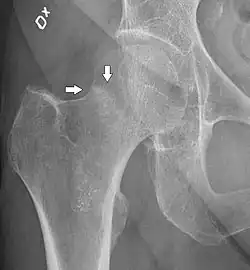

4) Данные рентгенологического обследования — выполняется рентгенография тазобедренного сустава в прямой проекции. Наличие линии перелома на рентгенограмме служит окончательным, объективным подтверждением предварительно выставленного диагноза. Иногда для постановки диагноза может потребоваться магнитно-резонансная томография или компьютерная томография.

В большинстве случаев достаточно выполнения рентгенограммы в прямой проекции. В ситуациях, когда есть подозрение на перелом шейки бедра, но оно не выявлено на рентгеновском снимке, следующим методом исследования является КТ. В редких случаях для подтверждения диагноза используется МРТ — диагностика.

Случай, демонстрирующий возможный порядок исследования изначально незаметных проявлений:

Заключение о виде перелома делается обычно на основании рентгенограмм во фронтальной проекции или КТ-картины. Правильное определение типа перелома позволяет выбрать тактику лечения, которая может существенно различаться для того или иного вида повреждения.